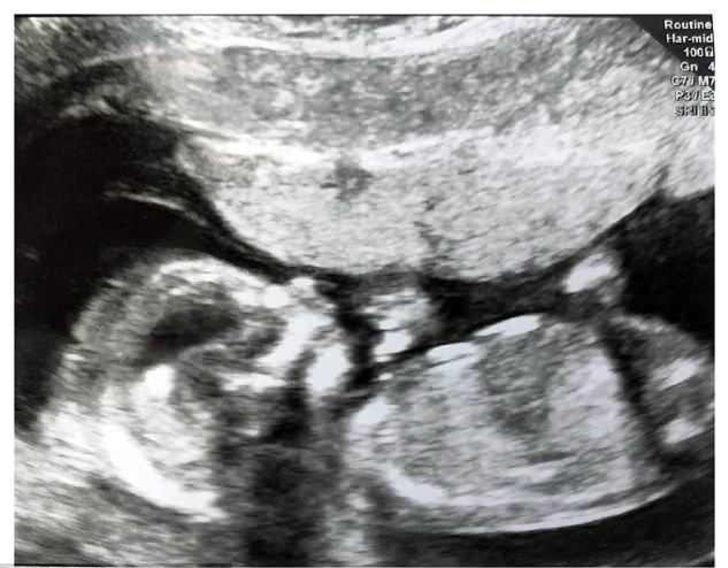

Yirmi çocuk annesi kadın 21. çocuğuna hamile

İngiltere'nin en büyük ailesi şaşkınlık yaratıyor. 20 çocuğu olan Radford ailesi 21. çocuklarının doğmasını bekliyor.

Yeni çocuklarının cinsiyetini YouTube'dan paylaştıkları video ile duyuran aile kız bebek müjdesi verdi.